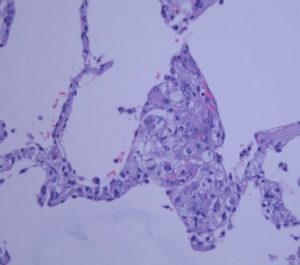

La criptococosis pulmonar se caracteriza por un cuadro febril de disnea, tos seca, sudoración nocturna y deterioro respiratorio progresivo. Las formas pulmonares graves presentan riesgo de diseminación al sistema nervioso central y otras localizaciones como la piel.

En el caso de Criptococcus neoformans, la detección del antígeno polisacárido de la cápsula a partir de muestras de suero, plasma, sangre total o Líquido cefalorraquídeo son usadas con mayor frecuencia debido a su alta sensibilidad como especificidad (>95%) principalmente en pacientes con VIH puede llegar a ser incluso mayor. Sin embargo, en este tipo de pacientes, se han descrito cepas de C. neoformans con poca cápsula en los que la concentración de antígeno puede ser anormalmente baja.